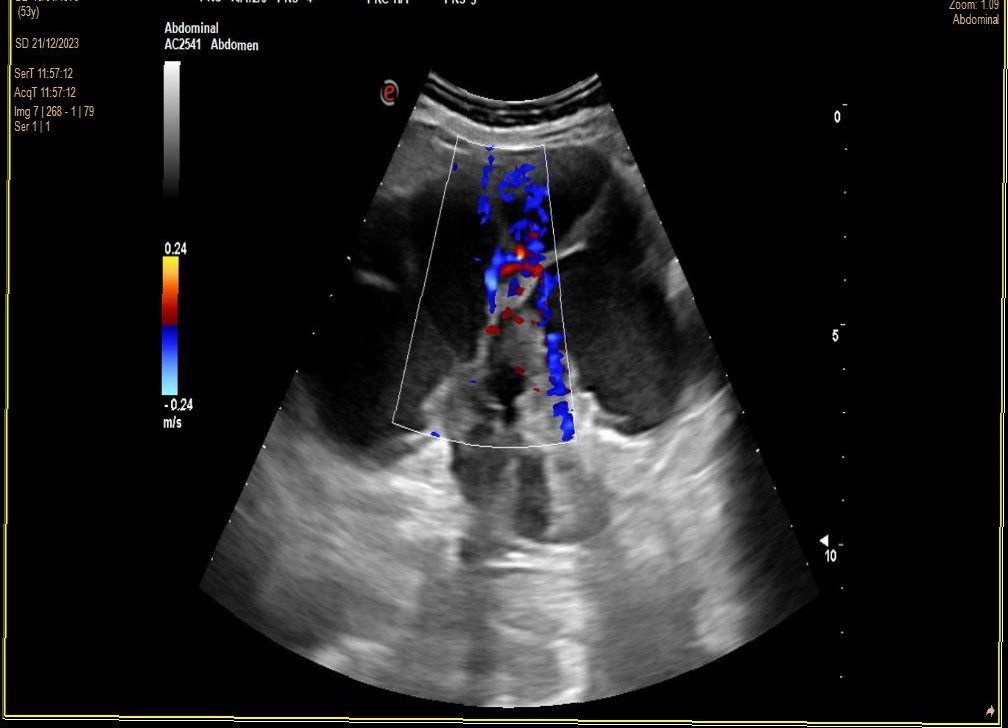

Derivación UHR (contacto telefónico). Ecografía Rx hospital. RD: Ecoestructura heterogénea. Diferenciación corticomedular alterada. Alteración morfológica. Dilatación hidronefrosi grau IV. No aumento de vascularización. RI: No se observan alteraciones.